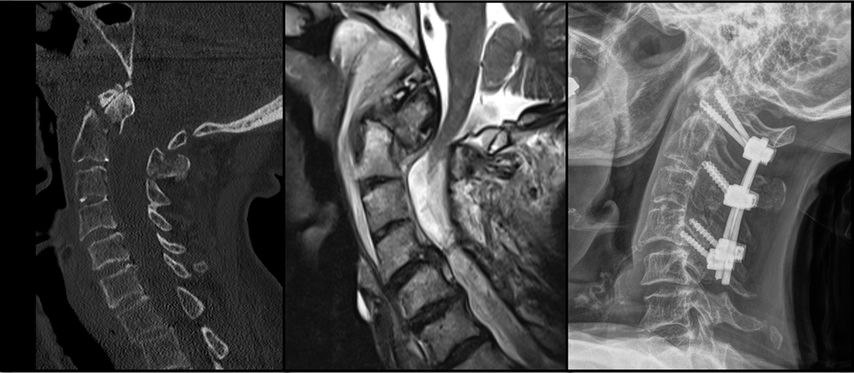

Abb. 1: CT und MRT eines pädiatrischen Patienten mit einer Typ-I-AOD und atlantoaxialer Dislokation nach Verkehrsunfall

AOD stellt die schwerste Verletzungsform im kraniozervikalen Bereich dar und ist für etwa 6–10% aller tödlichen Verletzungen der Halswirbelsäule verantwortlich. Sie tritt in über 30% der tödlichen Fälle nach Verkehrsunfällen auf und zeichnet sich durch eine hohe Letalität aus.5 Der häufigste Verletzungsmechanismus bei der kraniozervikalen Dislokation ist eine Hyperextension infolge stumpfer Gewalteinwirkung. Dabei kommt es häufig zum Riss der Membrana tectoria. Aufgrund des disproportionalen Verhältnisses zwischen Kopf und Körper sind pädiatrische Patient:innen bei Verkehrsunfällen mit hoher Geschwindigkeit besonders gefährdet. Atlantookzipitale Dissoziationen werden traditionell nach der Klassifikation von Traynelis et al.6 in drei Typen eingeteilt: Typ I beschreibt eine anteriore Verschiebung des Okziputs relativ zum Atlas, Typ II eine longitudinale Dislokation und Typ III eine posteriore Verschiebung des Okziputs gegenüber dem Atlas. Die aktuelle Harborview-Klassifikation erlaubt im Vergleich zum oberen Klassifikationssystem eine detailliertere Bewertung der Operationsindikation, da sie auf MRT-Befunden basiert und insbesondere den Grad der Dislokation berücksichtigt. Sie unterscheidet drei Verletzungstypen; TypI stellt eine stabile Verletzung dar, bei der häufig lediglich eine unilaterale Schädigung der kraniozervikalen Bänder vorliegt. In diesen Fällen ist eine konservative Behandlung in der Regel erfolgreich. Ab Typ II wird eine dorsale okzipitozervikale Fusion unter Verwendung von Plattensystemen empfohlen.